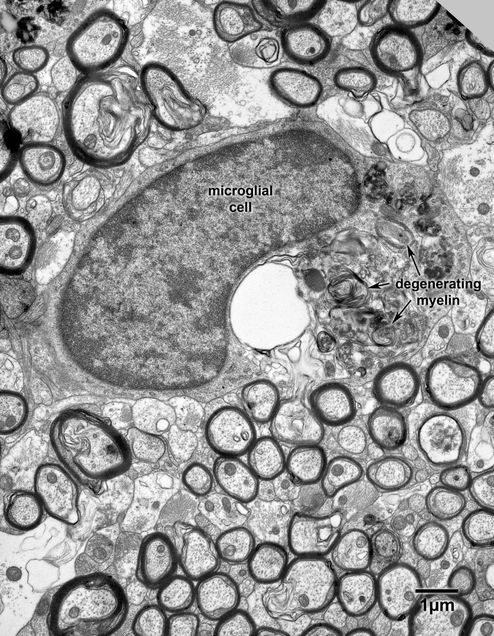

Figure 14.7

A microglial cell in the optic nerve of a 32 year old monkey. The microglial cell has phagocytozed a large amount of debris, some of which is obviously degenerated myelin.